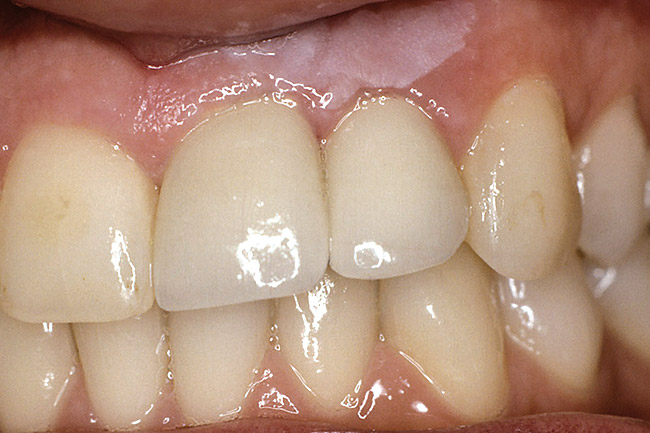

Accounting for this difference are the biology of the periodontium and the response of the bone and soft tissues when one tooth is lost rather than multiple teeth. In the case of a single-tooth loss, if a single-tooth implant is placed, the interproximal papilla levels will be determined by the height of the interproximal bone on the adjacent natural teeth, not the interproximal bone on the implant.1-3 In the average patient, the papilla height will be 4 mm to 4.5 mm above the interproximal bone on the adjacent natural teeth (Figure 1). Therefore, if the natural teeth have no bone loss, the papilla height after tooth loss will be similar to what it was before tooth removal because the average papilla height above bone between natural teeth is also 4.5 mm.4,5 The facial gingival margin around the implant, however, is not related to the bone on the adjacent natural teeth, but rather to the facial bone levels on the implant, as well as the thickness and position of the free gingival margin before tooth removal.6,7 For a single anterior implant, the least predictable soft-tissue outcome results when the adjacent natural teeth have interproximal bone loss because managing the papilla heights can be difficult.

Figure 1  The relationship of the interproximal papilla height to the interproximal bone of the adjacent tooth is 4.5 mm.

Figure 1